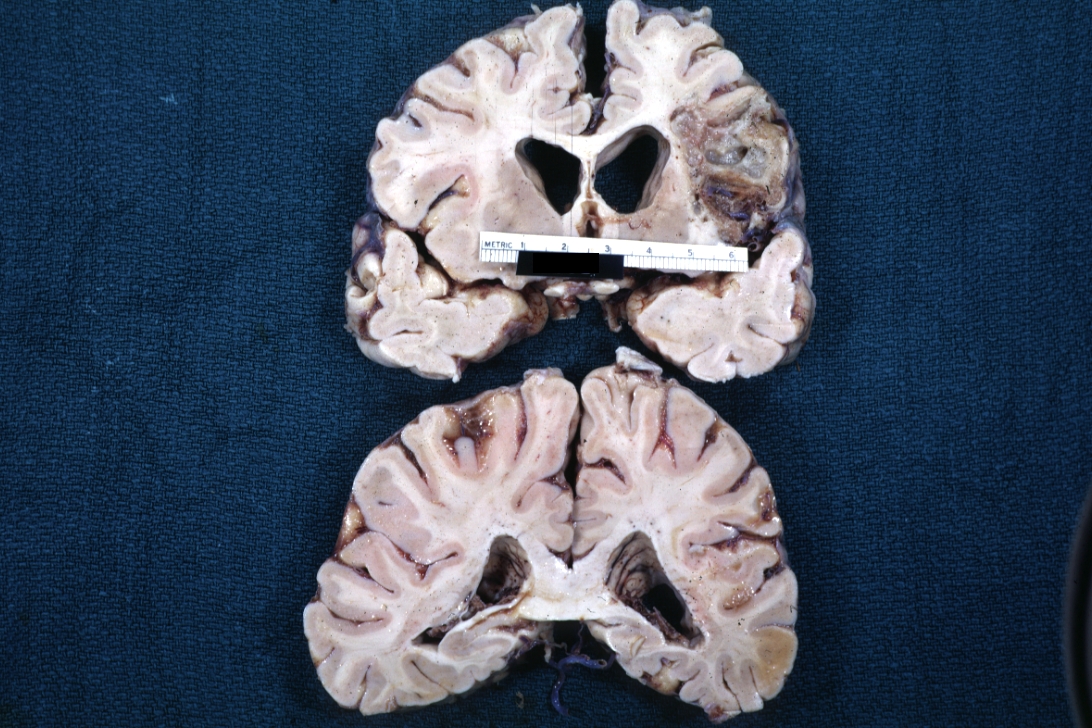

GROSS: NERVOUS: Brain: Abscess: Gross fixed tissue coronal sections cerebral hemispheres large abscess parietal lobe following pneumococcal meningitis